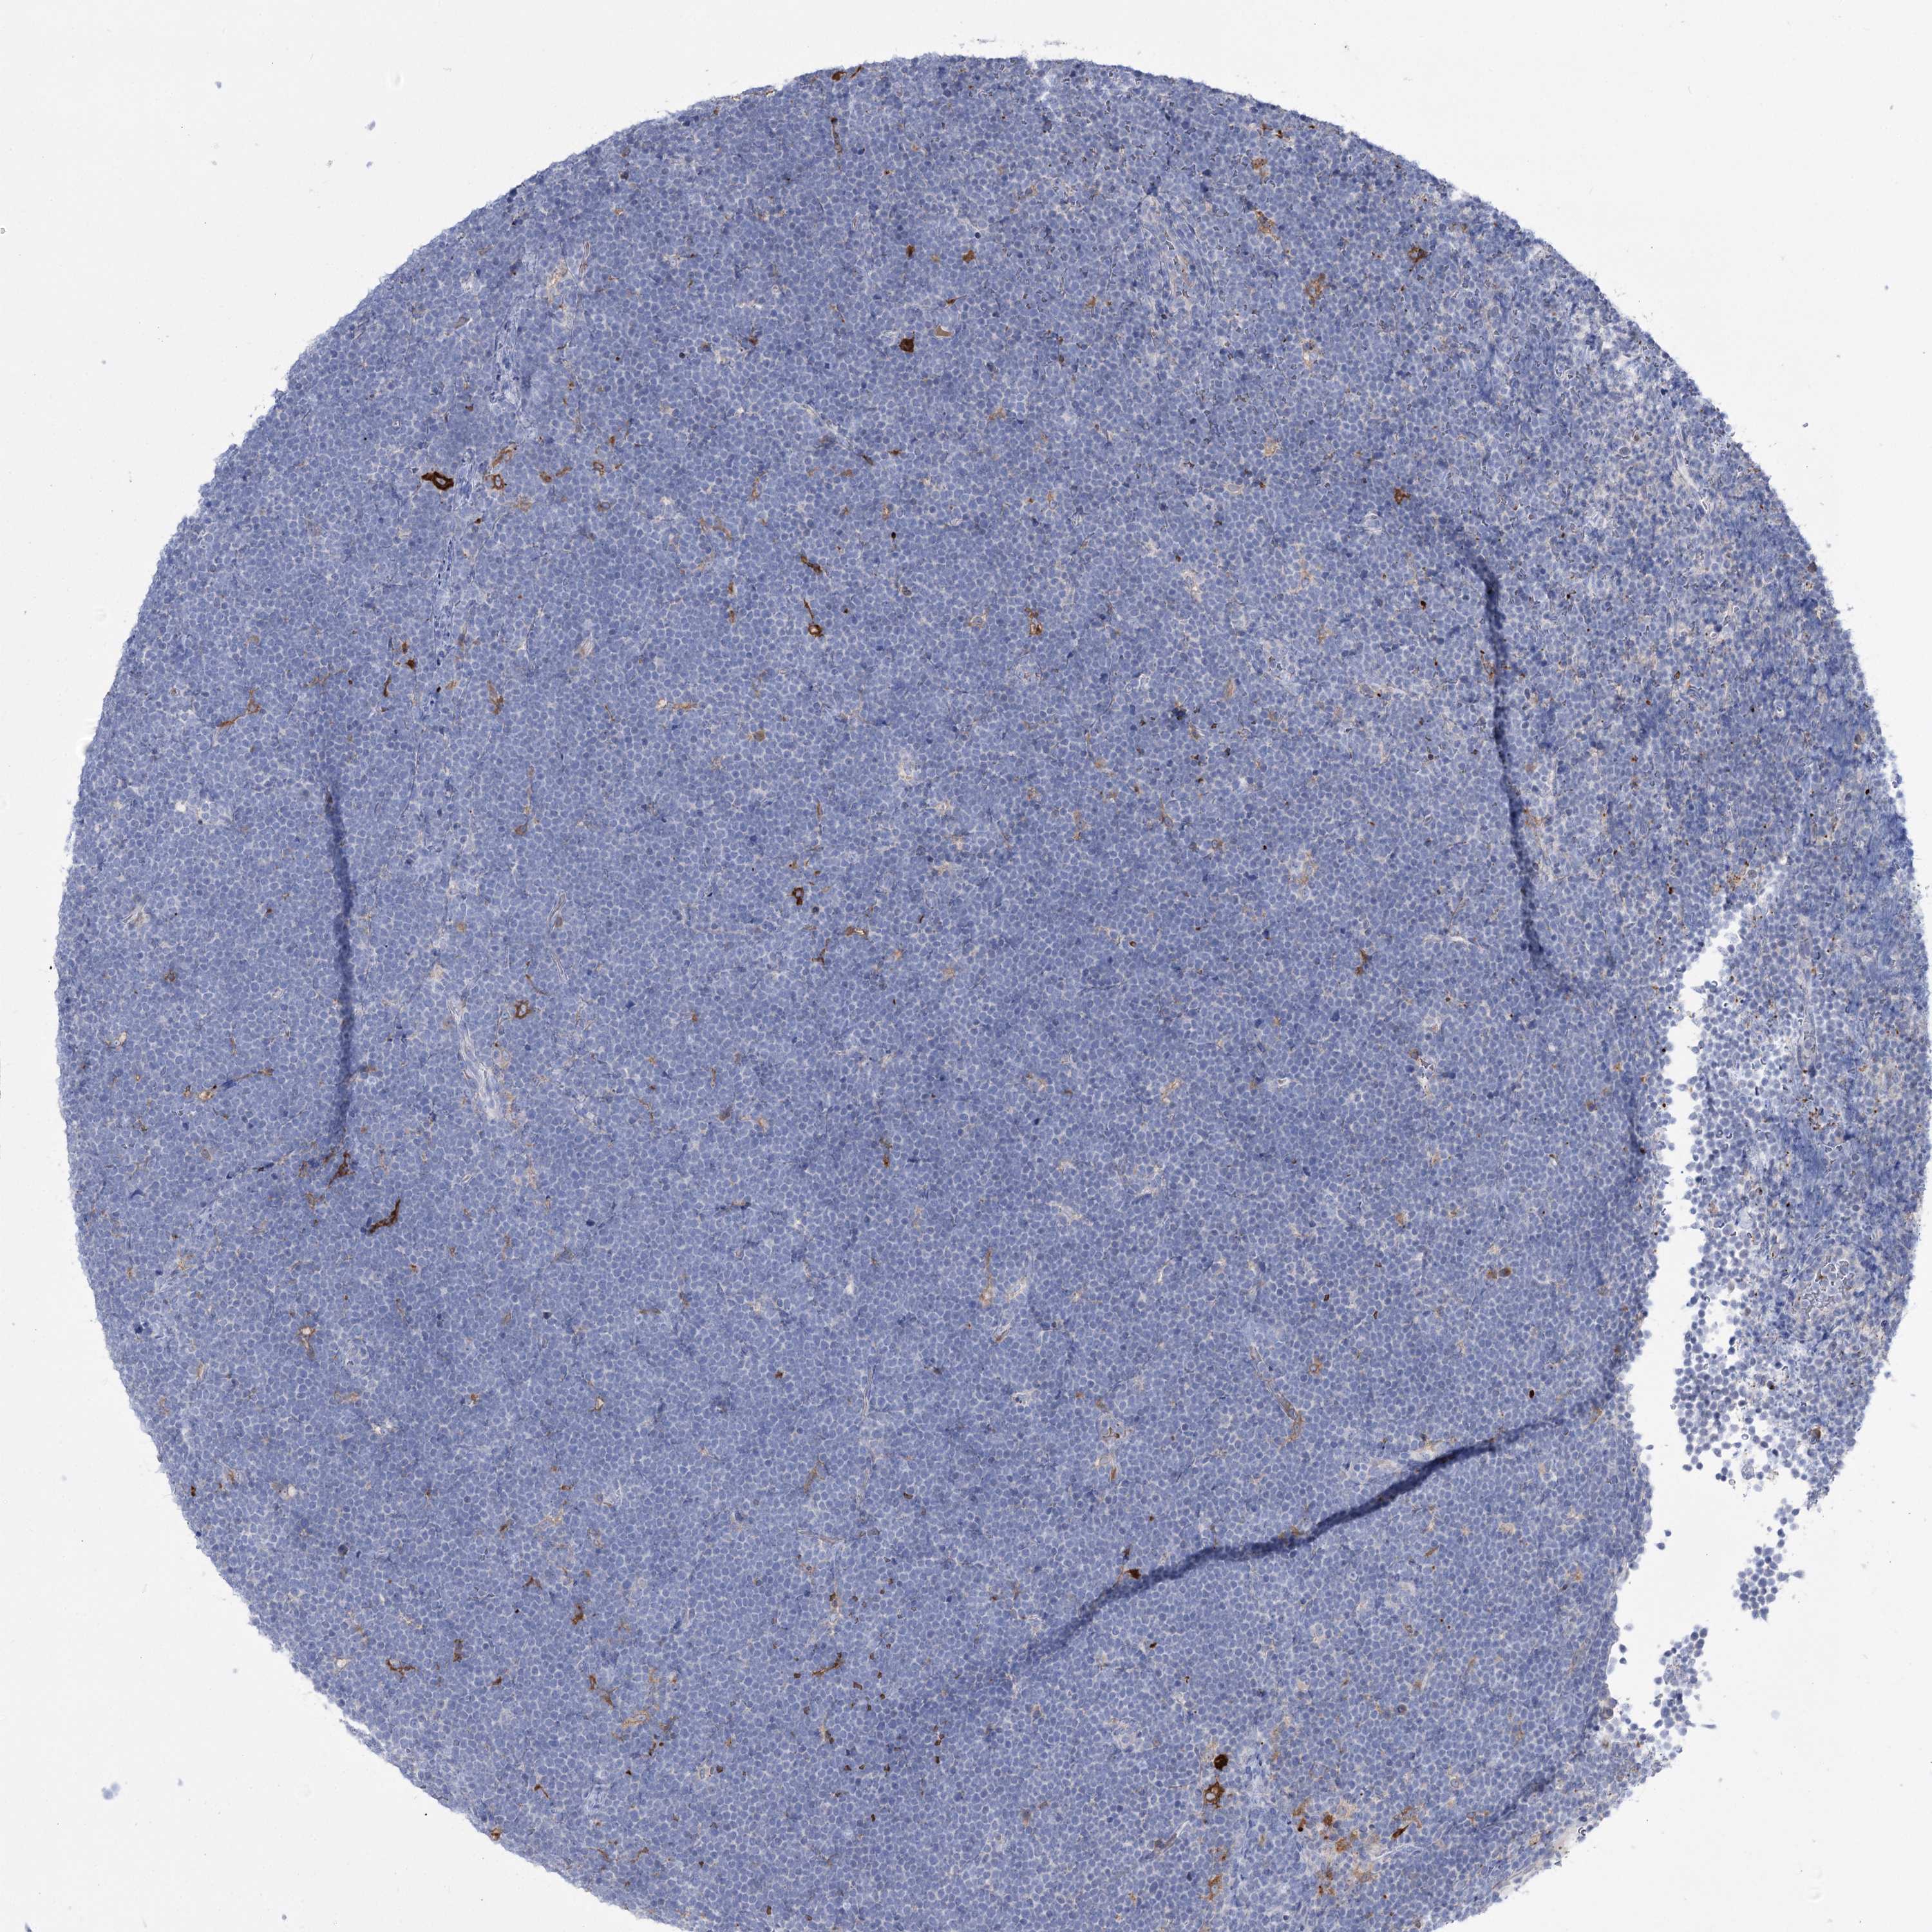

LYMPHOMA - Protein expressioni

A mouse-over function shows sample information and annotation data. Click on an image to view it in a full screen mode. Samples can be filtered based on level of antibody staining by selecting one or several of the following categories: high, medium, low and not detected. The assay and annotation is described here.

Antibody stainingi

Antibody staining in the annotated cell types in the current human tissue is reported as not detected, low, medium, or high, based on conventional immunohistochemistry profiling in selected tissues. This score is based on the combination of the staining intensity and fraction of stained cells.

Each image is clickable and will lead to virtual microscopy that enables deeper exploration of all samples and also displays staining intensity scores, fraction scores and subcellular localization as well as patient and tissue information for each sample.

Antibody HPA036514

Antibody HPA036515

Staining

High

Medium

Low

Not detected

Malignant lymphoma, non-Hodgkin's type, High grade

Malignant lymphoma, non-Hodgkin's type, Low grade

Hodgkin's disease, NOS